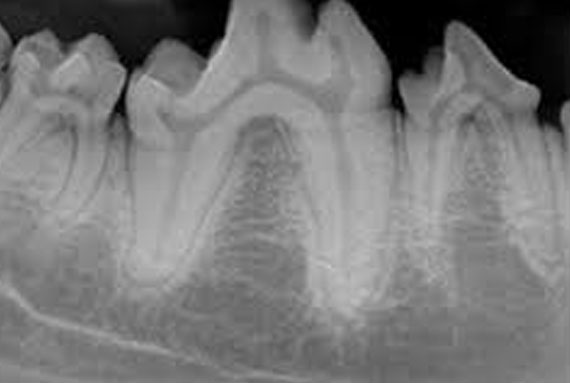

Dental

Dental radiographs and probing allow us to identify if any teeth need extracting. Our dental xrays are digital meaning a quick turnaround to view saving your pet anaesthetic time. We also use a Vet Tome machine that greatly reduces extraction time and saves bone. Our dental machine is similar to the one your dentist uses ensuring an optimal scale and polish is done.